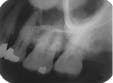

When the zygomatic process of the maxilla is superimposed on the roots of the maxillary molars (see Radiograph 4), another error occurs frequently with either technique. Too much vertical angulation will show this error in bisecting. Decreasing the vertical angulation by at least 10 degrees corrects it. With parallel technique, the key factor is improper placement of the film holder. Change the position of the film holder so the biting surface is flush with the occlusal and incisal surfaces.